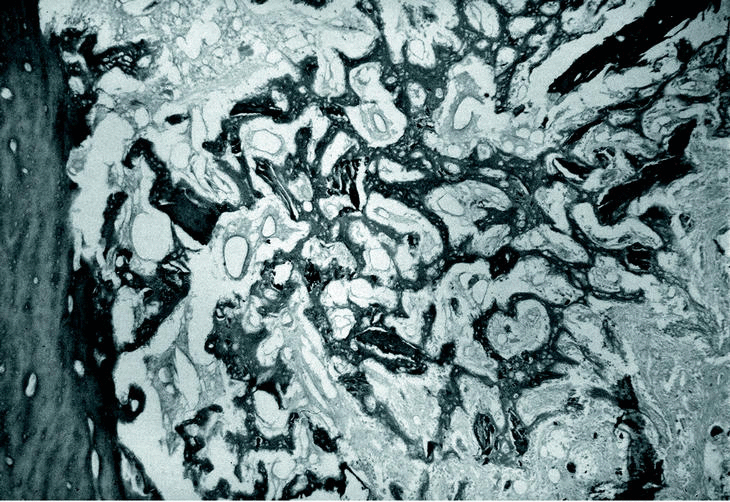

El estudio morfológico del canal medular reveló la presencia de hueso reactivo lamelar neoformado subperióstico (Fig. 2), osteoide inmaduro a nivel del endostio que engloba las trabéculas óseas con fenómenos de osteonecrosis y que se dispone en «encaje» sin ninguna organización (Fig. 3). También se vieron numerosas zonas de hueso necrótico en el interior del canal medular.

Figura 3. Osteoide inmaduro a nivel del endostio (H-E. 40x).